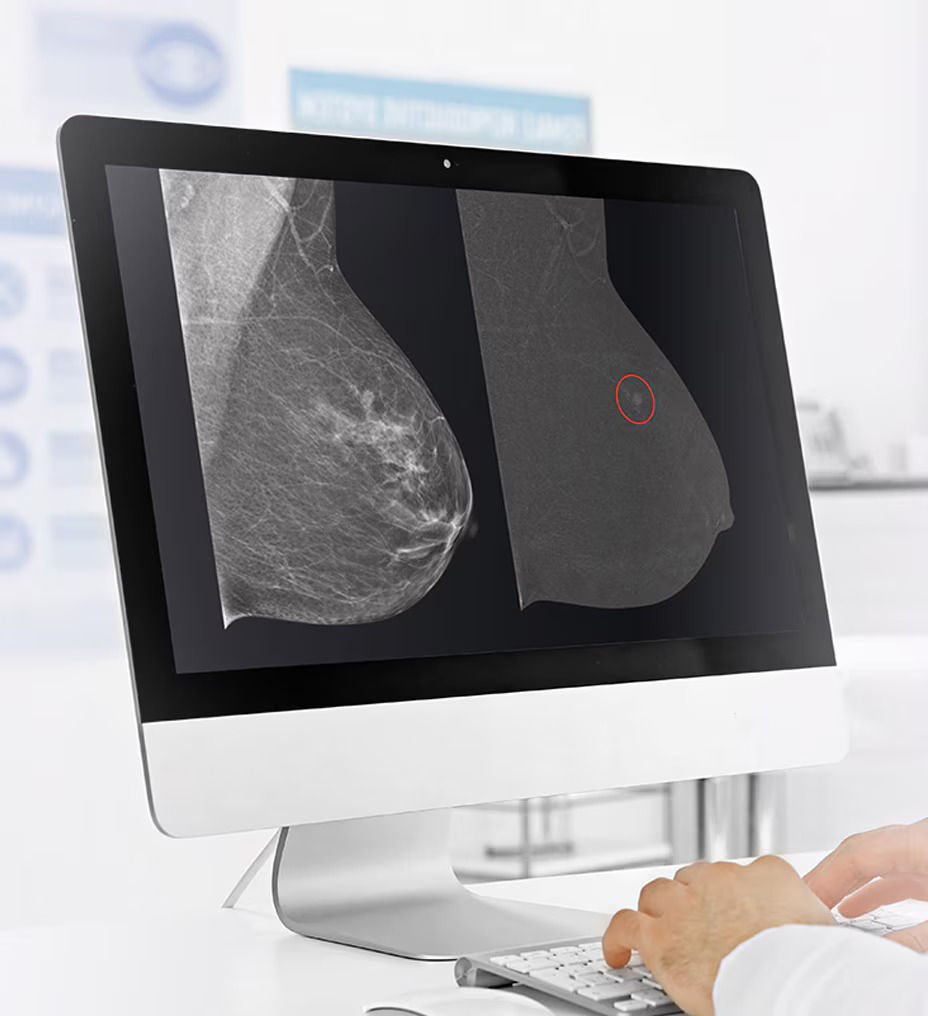

With over a decade of contrast mammography leadership worldwide, GE HealthCare’s contrast enhancing mammography (CEM) is a game changer in breast diagnostic imaging and biopsy care.

GE HealthCare pioneered this technology in 2010 and is associated with over 200 publications that demonstrate its clinical performance. GE HealthCare’s CEM combines the morphologic and density information similar to a conventional mammogram and the functional vascular information of a breast MRI1. It presents an opportunity to create and implement a more streamlined workflow to help diagnosis breast cancer early. In addition to increasing patient access, our CEM offering boasts high levels of sensitivity and specificity, allowing for the detection of lesions that would otherwise go undetected2,3,4. To ensure your practice can fully leverage the combined power of GE HealthCare contrast mammography solutions, we introduce Pristina Bright our comprehensive CEM package with complete support, from training to service, for your successful implementation.